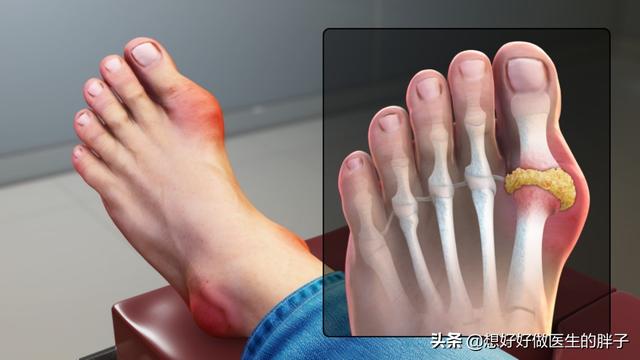

痛風この病気は、私たちの身体のプリン体代謝異常が生じ、尿酸が異常に上昇し、長期的に尿酸が上昇する。過飽和を形成することになる。尿酸塩の結晶。この尿酸塩結晶が体内に沈着し、徐々に増えていくことで、痛風の発作を引き起こす可能性がある。

而痛風発作は結晶性炎症反応の一部である痛風の発作が起きると、尿酸塩の結晶があちこちを汚してしまう。白血球しかし、尿酸塩の結晶は、特に鋭く、ちょうどその部分にある。白血球がそれを破壊しているのだ。攻撃部位に多くの炎症因子が放出されるため、患者は以下のような症状を示す。特に激しい、再燃部位の痛みそして、ローカライゼーションは迅速である。肿胀上へ。皮膚温が上昇する。また、患者によっては発症することもある。体温の異常。

すでに言われたとおりだ。痛風は患者に典型的な発赤、腫脹、熱感、痛みを引き起こす。痛風は最初の発作時に足の指に起こりやすいが、絶対的なものではなく、肘、膝、指、手首に起こることも多くなってきている。

痛風かどうかを判断する方法は、主に関節による。53%から70%の患者の発症当初は、第一趾の関節(足痛風と呼ばれる)が赤く腫れ、熱く痛み、通常は多発し、一部は複数の関節として現れることもある。固定性、非対称性で、次第に足首、膝、手首、肘などの大きな関節に浸潤することもある。

最初の症状は関節痛で、主に足、特に外反母趾に現れることが多い!

なぜ外反母趾なのか?理由は簡単だ。 自分の体のリンクを手に入れようとすればいい。この関節部分は比較的温度が低いことがわかるだろう。物理を学んだことがある人や溶解度について知っている人なら、温度が高いほど溶解度が大きく、逆に温度が低いほど溶解度が小さいことを知っているだろう!私たちが普段、砂糖と塩を水に溶かすように、砂糖と塩を水に溶かすのは温度が高い方が簡単だろうか?そして、温度が低いほど溶けにくいのではなく、沈殿しやすいのだろうか?この外反母趾の関節は、温度が低ければ低いほど、尿酸塩の結晶が形成されやすくなり、組織の損傷や炎症性の痛みを引き起こす!

また、これは外反母趾の関節は、外傷に対して最も脆弱な関節でもある。また、ちょっとした外傷が関節周辺のpHを変化させ、尿酸結晶の沈着を助長することもある。もちろん、痛風による関節痛はここに限ったことではなく、足背、足首、膝などが一般的な部位であり、通常は左右対称性はなく、足を触ると発赤、腫脹、熱感があり、さらに触ると熱い。

足指は尿酸塩がたまりやすい部位で、痛風に襲われると、文字通り耐え難い痛みが走る。

痛風の急性発作では、しばしば罹患した関節(最も一般的なのは母趾と足背)に著しい局所の発赤、腫脹、熱感、疼痛、機能障害がみられる。

痛風の発作は、足の母趾(第一中足趾節関節)などの関節の突然の腫脹と激痛の日として現れます。冒頭で述べたように、急性痛風は患者の高尿酸血症の存在が先行しなければならず、高尿酸血症を無視すると激しい痛みを伴う痛風に発展する可能性がある。

すべての関節の中で、痛風が最も発症しやすい部位は第一中足趾節関節であり、痛風を患う人の約70%が最初に発作を起こす場所である。

上記の条件を満たす関節は基本的に四肢の関節であり、第1中足趾節関節は心臓から最も遠く、体温が最も低い。また、第1中足趾節関節は歩行、体重の支持、体のバランスの維持など一連の役割を担い、負担や圧力が大きいため、痛風の発作が最も起こりやすい部位となる。

一般に、痛風性関節炎の急性発作は非常に激しく、この時の痛みを表現すると、"風が吹いただけでも非常に痛い "となる。これが痛風の語源である。痛風発作の初期には、痛みは徐々に増していき、足を布団につけるだけでも我慢できないほどの痛みが起こります。

- 急性痛風の症状には、痛み以外に、通常、発作部位の発赤、腫脹、局所の温感、著しい圧迫痛が含まれる。第1中足趾節関節に急性痛風発作が起こると、足が腫れて靴が履けなくなり、痛みが激しくて歩けなくなります。